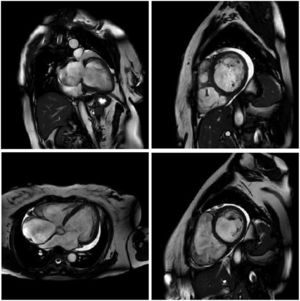

MRI is a high-quality and well-established test for assessing cardiac anatomy and function (Figure 2). It is able to determine cardiac chamber volume and degree of contractility, as well as to diagnose thrombus if present. The most effective analysis of cardiac tissue is by infusion of gadolinium, which can identify and quantify areas of the heart with fibrosis.82,83

Cardiac magnetic resonance imaging showing congestive heart failure/cardiomyopathy of probable inflammatory etiology (Chagas myocarditis), with significant dysfunction and increased biventricular diameters, significantly dilated right atrium and tricuspid regurgitation, dilated left atrium and mitral insufficiency, and pericardial effusion.

Some patients develop malignant arrhythmias without global ventricular systolic dysfunction but with myocardial fibrosis that can be detected by MRI.84,85